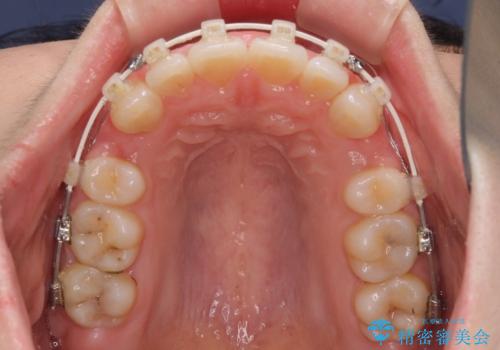

- 審美装置

上下左右第一小臼歯4本の抜歯を行い、ワイヤー装置による矯正治療を行うこととしました。

元々上下正中の位置はずれていましたが、治療中によりズレが大きくなったので、元の位置に戻すため治療期間を余計に要しました。